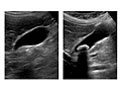

• Abdominal ultrasound. An abdominal ultrasound is the best test to confirm gallstones. In this test, a technologist moves a wand across your belly to create pictures on a video monitor. This test may reveal other problems with the gallbladder or bile ducts. An ultrasound image of a gallstone often is the only test needed to find and evaluate gallstones.